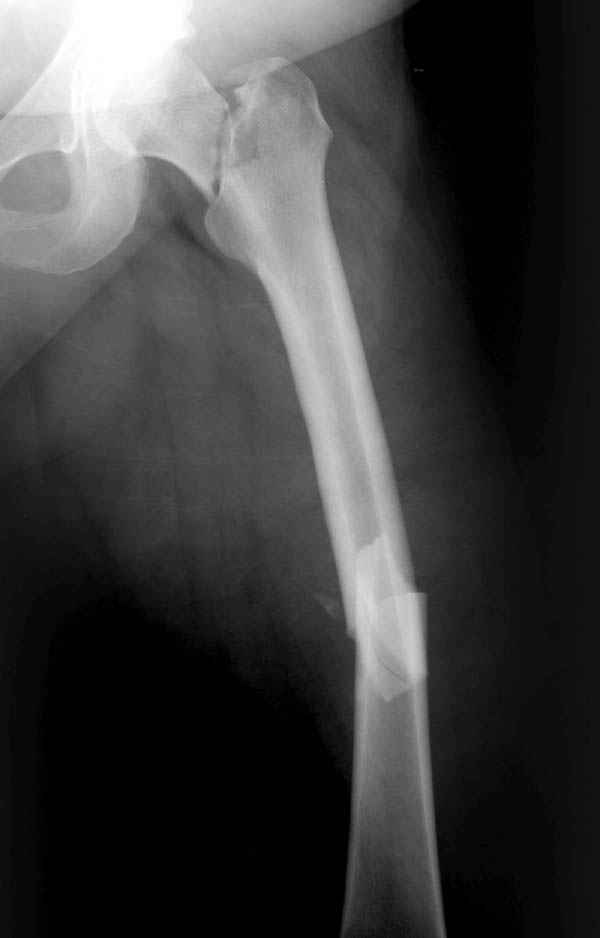

Несмотря на пессимистические прогнозы, у молодых

коррегирующая вальгусная остеотомия является более

приемлемым.

Представленные случаи доказательства тому, что еще

имеется резервы на восстановление даже у 5-6 месячных ложных суставов шейки.